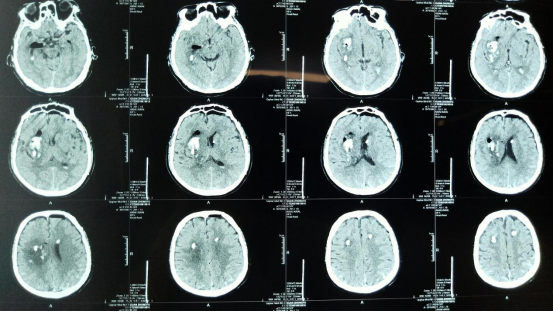

术后影像

手术由高风全副主任医师和王云龙副主任医师共同完成,在神经外科机器人引导下,定位数据从术前CT上获得,以此作为定位依据确定穿刺点和靶点完成手术设计,精准打靶,成功完成立体定向下脑出血精准穿刺引流手术,术后当日患者即恢复自主意识。

附属三院神经外二科引进的神经外科机器人,可以让手术精准于毫厘之间,使得神经外科领域颅脑深部病变、颅底病变、脊髓病变、功能区病灶等手术创伤小、恢复快,让患者受益最大化。手术导航系统联合启用神经内镜、显微镜这两大元素,成功开启了神经外科精准医疗时代。